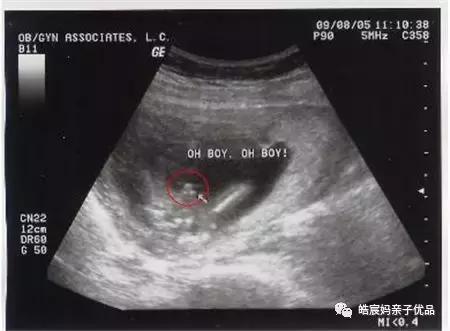

一般在用早孕棒测出怀孕之后,或者是用排卵试纸检测到呈阳性时就可以马上去医院做B超了,B超是诊断出怀孕的最正确可靠的方法。最早是在怀孕5周就能检测出来,就是在月经过期一周,在B型超声波上就会显示出子宫里面有圆形的光环,这也叫做妊娠环,环内的暗区就是羊水,其中还能够看见有节律的胎心搏动。

最早的一次B超检查是在怀孕早期,在停经6周之后。除了做一些妇科常规检查之外,还需要通过B超检查来确定宫内妊娠的正常。像宫腔内探查不到任何妊娠现象,而在子宫腔外探到异常的包块,结合一些其他的临床表现和实验室检查结果就可以考虑是不是宫外孕的可能。所以在怀孕早期通过B超能够明确是否是正常的妊娠,以及双胎或者葡萄胎。

如果要做B超排出宫外孕,最早是在月经错后的10天以上再去,通过超声检查,就可以诊断出胎囊是否在宫腔内,这样就能够排出宫外孕的情况。不过因为时间很短,可能胎囊不显影,所以结果不会太准确。

一般是在怀孕8-12周就能够看到胎囊了,在这个时间段做个B超检查就能够确定是否是宫外孕,不过也有可能会因为孕囊着床晚,或者发育迟,检测不到孕囊。所以为了保险,可以等到月经推迟七天以上,再去医院检查是否有宫外孕的情况。